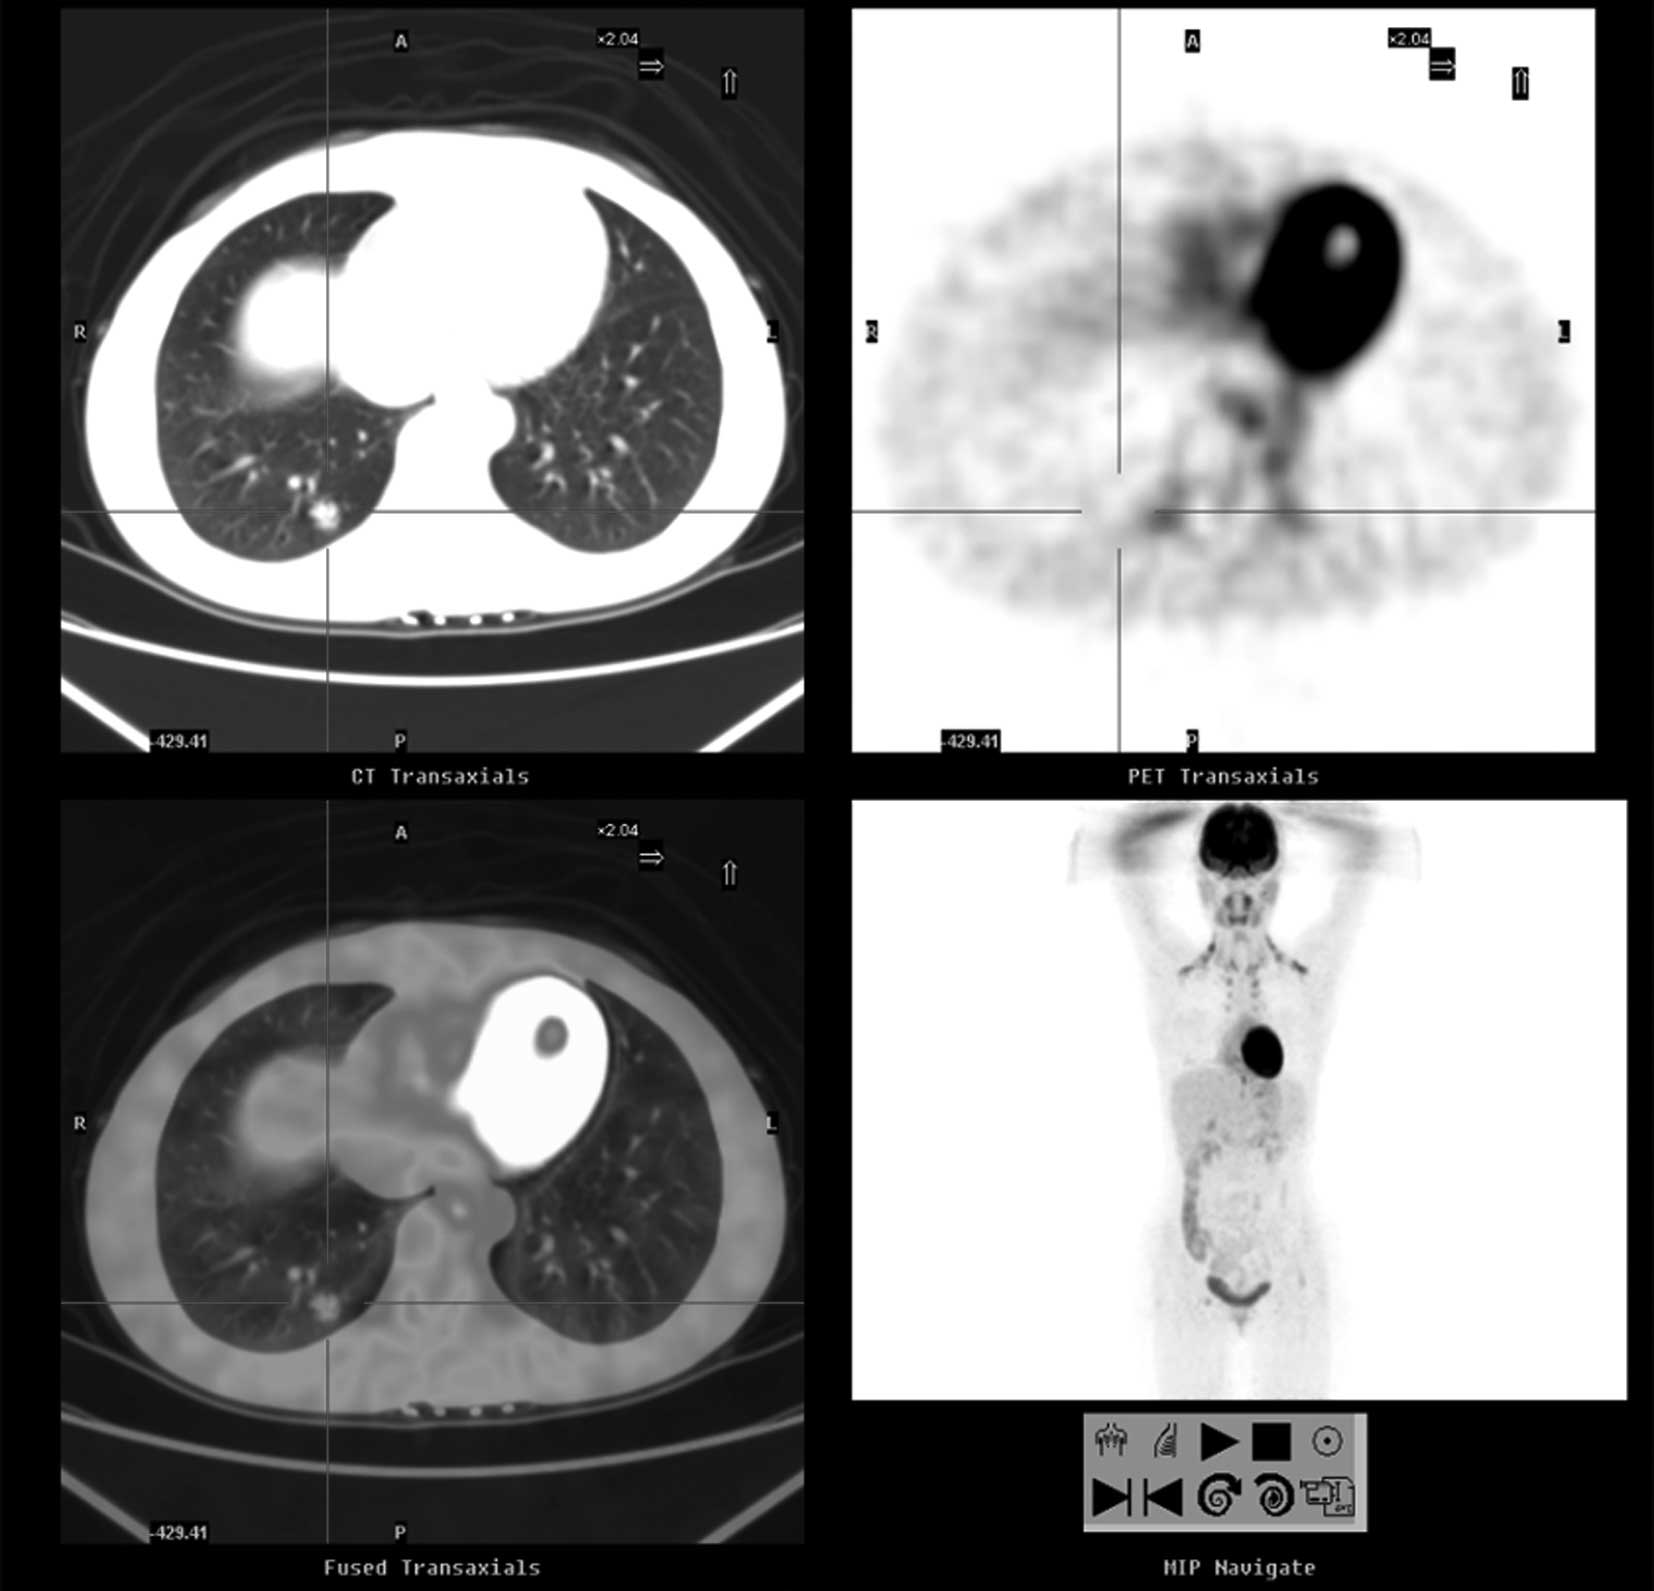

A case of pulmonary sclerosing hemangioma with low 18FDG uptake in PET

Pulmonary sclerosing hemangioma (PSH) is a relatively rare benign neoplasm, often asymptomatic and presenting as a solitary pulmonary nodule on radiological imaging studies. In the present case report, we examined a case of PSH in a young adult female, and reviewed the literature pertaining to PSH with an emphasis on 18F-fluorodeoxyglucose positron emission tomography/computed tomography (18FDG PET/‌CT) and pathology. Immunohistochemical staining was also performed to confirm the diagnosis of sclerosing hemangioma. The results revealed that the tumor cells were immunopositive for epithelial membrane antigen, thyroid transcription factor-1 and vimentin and cytoskeleton 7. The patient recovered and was discharged. Thus, 18FDG PET/CT may be used in the diagnosis of a solitary benign pulmonary nodule.

Figure 1

Figure 2

Figure 3

Figure 4